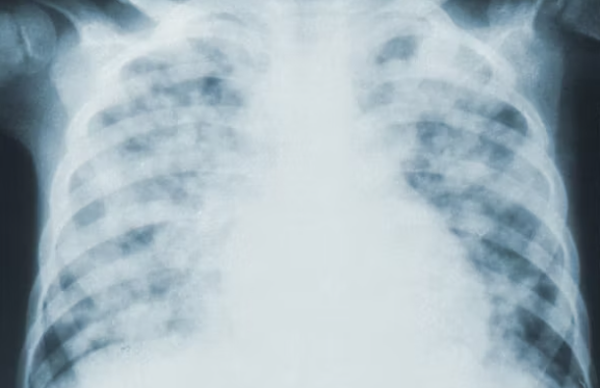

마이코플라즈마 폐렴이란?

마이코플라즈마는 마이코플라즈마속에 속하는 세균을 두루 부르는 명칭입니다. 분류상 세균과 바이러스의 중간 성질을 가지고 있으나 세균으로 분류하고 있습니다. 마이코플라즈마 폐렴은 대개 증상이 경하고 입원이 필요하지 않습니다. 또한 마이크로라이드계 항생제 치료에 효과가 있으나 2000년 이후 내성 폐렴균의 출현이 발견되었다고 보고된 바 있습니다.